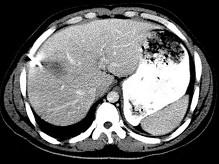

下列图像最佳诊断是什么 ( )A.阿米巴肝脓肿B.原发性肝癌C.肝转移瘤D.肝硬化E.脂肪肝

问题 下列图像最佳诊断是什么 ( )

选项 A.阿米巴肝脓肿 B.原发性肝癌 C.肝转移瘤 D.肝硬化 E.脂肪肝

答案 A